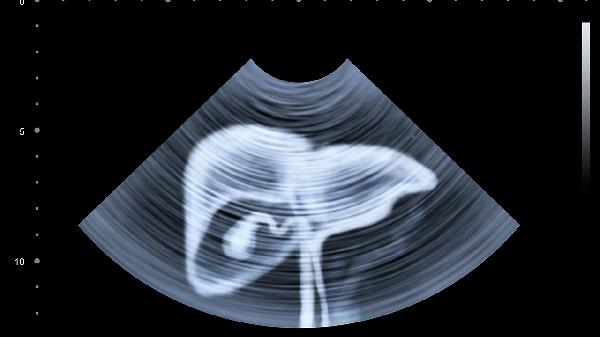

5、术前检查

术前通常需要进行血常规、凝血功能、肝肾功能、心电图、胸片等常规检查。根据手术类型可能还需要进行超声、CT等影像学检查。这些检查有助于评估手术耐受性和制定个性化手术方案。